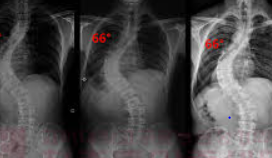

1. 관찰: 경미한 척추측만증의 경우, 특별한 치료 없이 정기적인 의사 상담과 X-선 검사로 진행 상황을 추적하는 것이 충분할 수 있습니다. 이는 만곡이 20도 미만일 때 주로 고려됩니다.

2. 보조기 착용: 만곡이 20도에서 40도 사이이며, 아직 성장 기간이 남아 있는 환자에게는 보조기를 착용하여 만곡의 진행을 막고 교정하는 방법이 사용됩니다. 보조기는 척추의 균형을 유지하고 추가적인 만곡을 방지하는 데 도움을 줄 수 있습니다.

3. 수술적 치료: 만곡이 심하거나 보조기 착용으로 개선되지 않는 경우, 수술적 치료가 필요할 수 있습니다. 수술은 척추의 만곡을 교정하고 고정시키는 것을 목표로 하며, 이는 주로 40도 이상의 만곡에 적용됩니다.